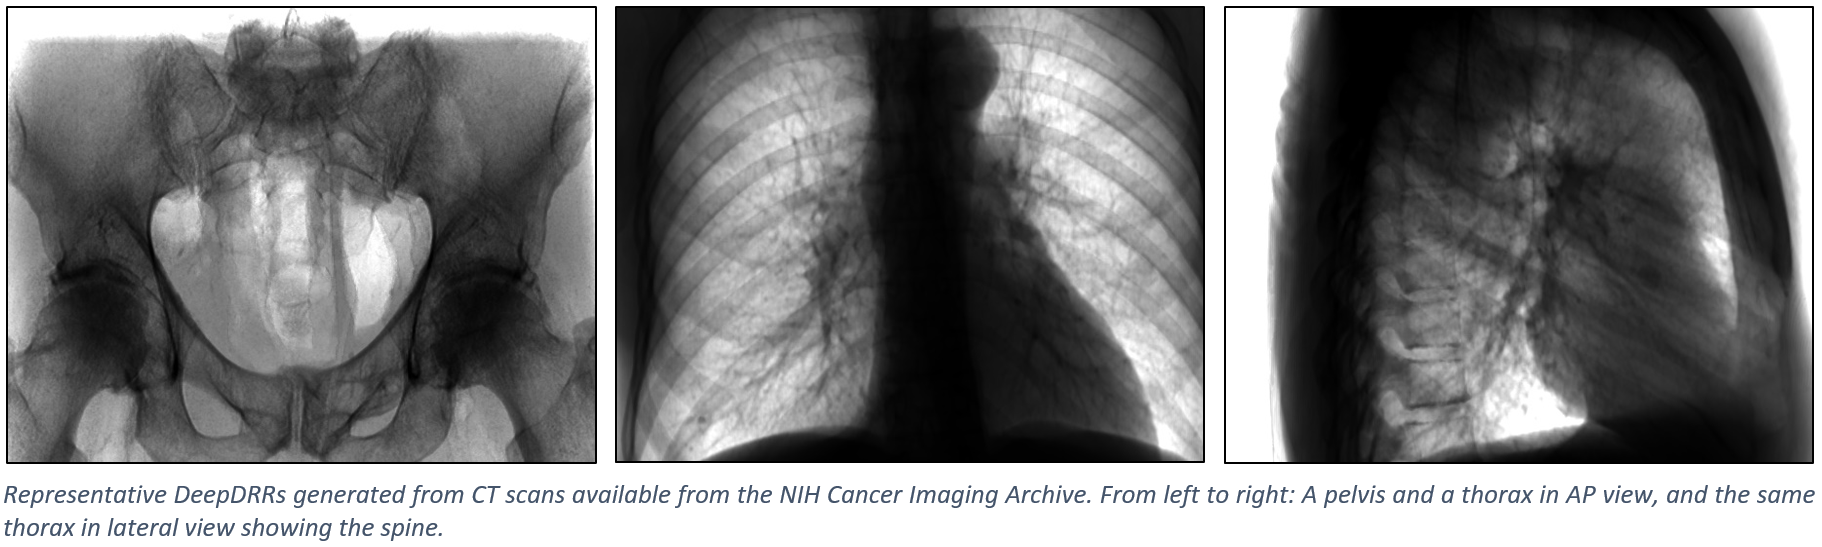

The figure below shows representative radiographs generated using DeepDRR from CT data downloaded from the NIH Cancer Imaging Archive. Please find qualitative results in the Applications section.